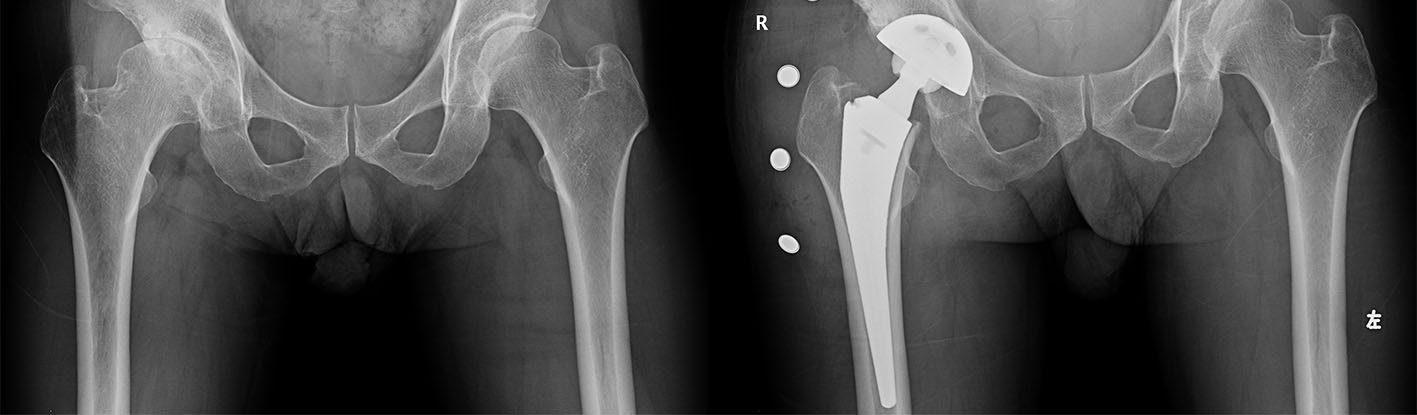

术前术后X-ray

57岁的姜先生就是湘雅系统首位受益于此手术的患者,他在过去5年反复出现右侧髋关节疼痛,且开始出现了跛行症状,诊断为“右侧股骨头坏死”,被当地医院告知后半生将坐轮椅终生残疾,因此慕名来我院就诊,吴松教授、沈民仁副教授及彭智主治医师在综合评估患者情况后,决定为患者采用最为先进的SuperPath技术,实施微创换髋,切口长度仅6cm,术中分离软组织过程中不需要切断任何肌肉和肌腱,从而为患者术后快速康复提供良好的肌张力,手术用时仅1个半小时,术中出血较传统手术明显减少。

SuperPath技术是换髋历史上的真正微创,患者最快术后几小时即可下床,大大缩短了患者住院天数,手术效果和术后恢复速度都令人满意。